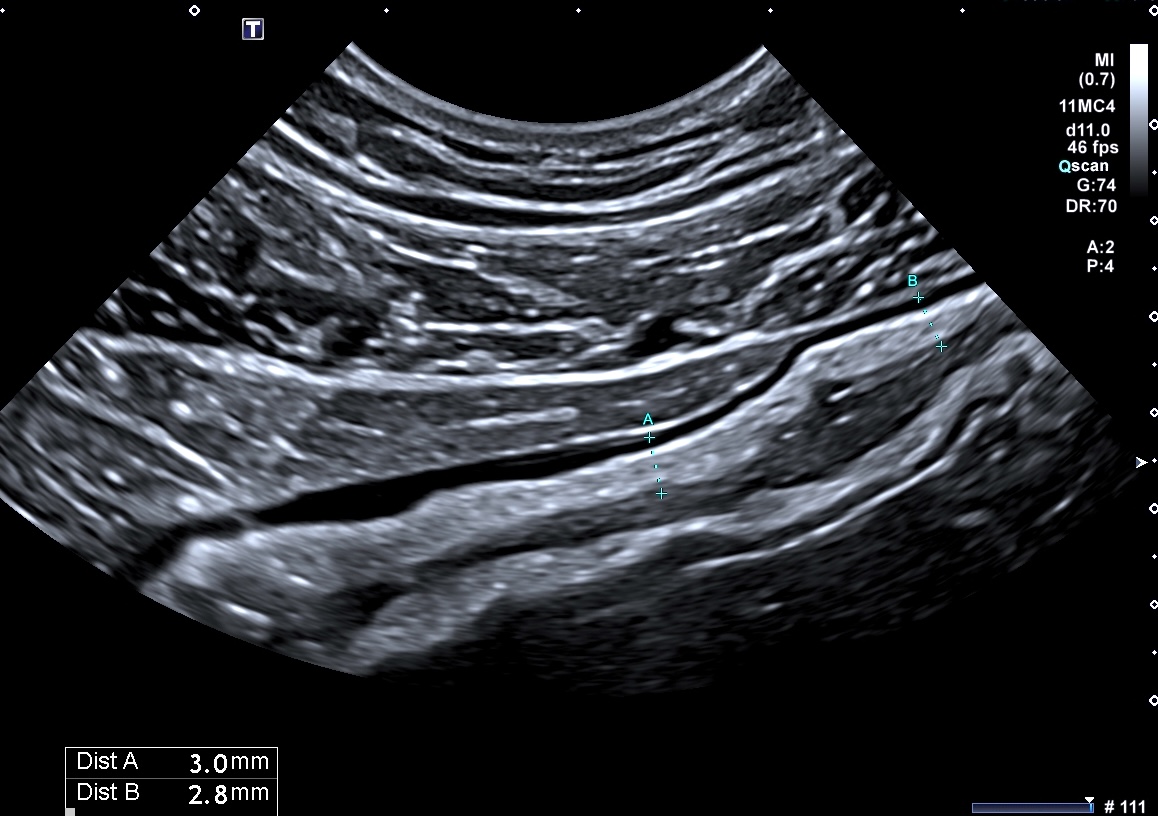

Exemple de paroi de 5 mm avec début de la disparition de la structure en couches (le contraste entre la muqueuse et la sous muqueuse est moins visible)

L'épaississement est encore plus important (8 mm), la surfacede la lumière devient irrégulière